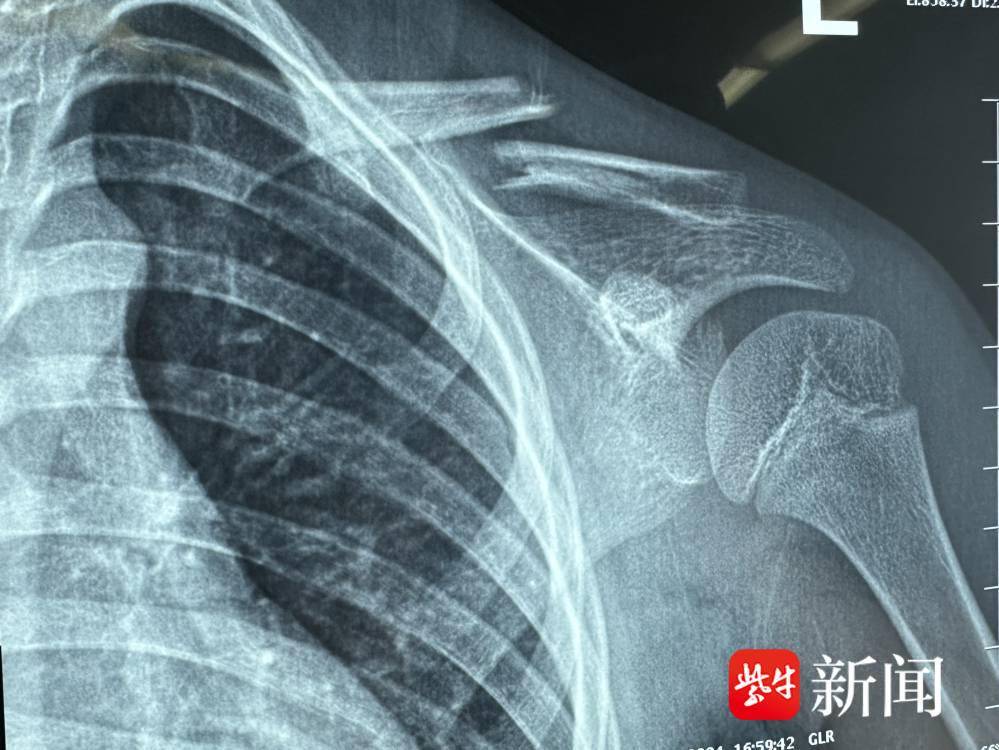

29日,院方介绍,4月20日傍晚,小欣和家人来到家附近的公园里玩。看到转转椅,她迫不及待坐了上去。然而,由于转转椅旋转速度过快,小欣不慎从椅子上摔下,左肩着地,瞬间疼痛难忍、大哭不止。家人急忙将她送到当地医院就诊,经拍片检查确诊为“左锁骨骨折”。医生当时建议进行手术切开复位内固定治疗。

接诊的创伤骨科副主任医师王春秋对小欣的病情,进行了仔细分析。他告知家属患儿骨折断端错位比较严重,如果治疗不当或延误治疗,可能会导致发育畸形、短肩等问题,甚至需要采用创伤更大的切开复位内固定方法。针对孩童的生长发育特点和手术依从性,建议采取闭合复位弹性髓内钉术。

在充分了解相关情况后,小欣的家长决定立即接受复位手术。4月25日,王春秋在基础麻醉下为小欣“接骨”复位。在患处点位“进针”,将弹性髓内针插入髓腔,闭合复位经皮髓内针固定,避免破坏软组织和剥离骨膜影响骨折端血运。手术过程中,医生们精准操作,将创伤和疼痛降到最低。